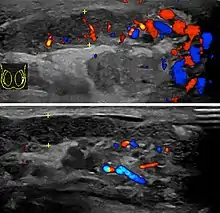

Diagnosis is typically based on symptoms.[1] Conditions that may result in similar symptoms include testicular torsion, inguinal hernia, and testicular cancer.[1] Ultrasound can be useful if the diagnosis is unclear.[1]

Epididymitis usually has a gradual onset. Typical findings are redness, warmth and swelling of the scrotum, with tenderness behind the testicle, away from the middle (this is the normal position of the epididymis relative to the testicle). The cremasteric reflex (elevation of the testicle in response to stroking the upper inner thigh) remains normal.[1] This is a useful sign to distinguish it from testicular torsion. If there is pain relieved by elevation of the testicle, this is called Prehn's sign, which is, however, non-specific and is not useful for diagnosis.[13] Before the advent of sophisticated medical imaging techniques, surgical exploration was the standard of care. Today, Doppler ultrasound is a common test: it can demonstrate areas of blood flow and can distinguish clearly between epididymitis and torsion. However, as torsion and other sources of testicular pain can often be determined by palpation alone, some studies have suggested that the only real benefit of an ultrasound is to assure the person that they do not have testicular cancer.[14]: p.237 Nuclear testicular blood flow testing is rarely used.